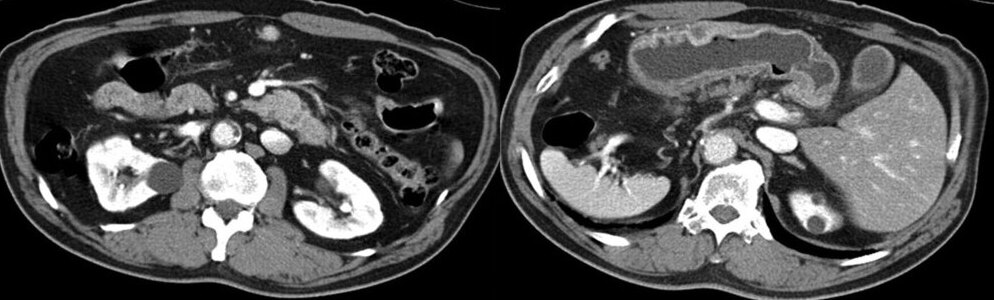

КТ диагностика тубоовариального абсцесса: Подходы и изображения

Раздел: Объективный взгляд